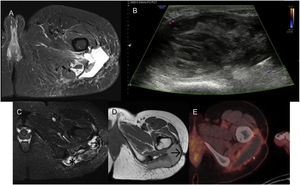

MRI (Fig. 2A) and CT scans (Fig. 2B) were performed, revealing a heterogeneous collection compressing the sciatic nerve in the proximal third of the leg. Given the clinical stability, conservative management was determined and evolutionary studies were performed over two years, during which time the collection maintained a similar volume, modifying internal signal probably due to haemoglobin degradation. The patient was admitted for pain and a PET-CT scan was performed (Fig. 2C), revealing a peripheral hypermetabolic component. A chocolate-coloured fluid was evacuated and a partial resection was performed, along with capsular dissection to the point where it was severely adhered to the sciatic nerve.

A) MRI heterogeneous collection with hypodense capsule (→). B) CT: predominantly hypodense collection, with peripheral enhancement (→). C) PET: peripheral hypermetabolic component observed. D and E) Post-surgical MRI: less voluminous collection and increased signal hyperintensity on T2 (*), corresponding to partial resection and new CEH formation.

An MRI study one month after surgery (Fig. 2D) showed a collection with a smaller volume yet similar characteristics, compatible with partial resection and a newly formed CEH. Subsequently, a total hip prosthesis was fitted due to chronic osteomyelitis. No further imaging tests were performed given the patient’s positive progress.

An ultrasound (Fig. 3A) and MRI (Fig. 3B) were performed, revealing an extensive lesion in the subcutaneous cellular tissue of the lateral aspect of the pelvis and root of the right thigh. The lesion was polylobulated and surrounded by a markedly hypointense thick capsule on all sequences. The content was highly heterogeneous, with a markedly hyperintense component on T1-weighted sequences.

A) Ultrasound and B) MRI: lesion in the subcutaneous cellular tissue of the lateral aspect of the pelvis and root of the right thigh, polylobulated, surrounded by a markedly hypointense thick capsule (→) on all sequences. The content is highly heterogeneous, with a hyperintense component (*) on the T1-weighted sequences. C) After intravenous contrast administration, central filiform enhancement is seen (→), with no peripheral or nodular enhancement.

After administration of paramagnetic contrast (Fig. 3C), central filiform enhancement was observed with no peripheral or nodular enhancement.